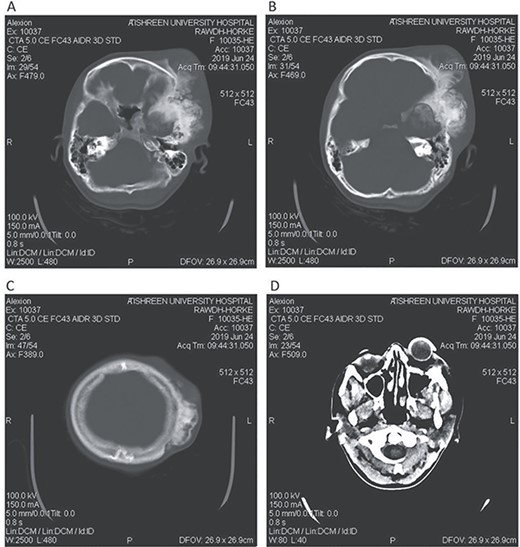

CT head bone window (A–C). A. Invasion of the frontal bone. B. Invasion of the orbit. C. Invasion of the parietal bone. D. Invasion of the sphenoid, temporal and parietal bones.

A 17-year-old female presented with a history of osteosarcoma that was confirmed after undergoing a surgery to remove an enlarging bone tumor in the left temporal region 2 years ago. She later got pregnant and delivered her child but never got back for a checkup until she was admitted to our hospital with a severe and unresponsive to medication headache that progressed over the course of 6 months and blurred vision that progressed to complete left-sided vision loss. Physical examination revealed a tough and mobile yet fixed at the base 7-cm mass towards the left of the frontal bone. Many more masses were revealed in the left side of the skull including the anterior cranial fossa, orbit, base of the skull and the left part of the occipital region where the previous procedure was performed (Fig. 1). These masses had been increasing in size probably under the influence of pregnancy hormones causing pain that radiated along the orbital and maxillary branches of the left trigeminal nerve. Physical examination and past medical history were otherwise unremarkable. Laboratory tests were all normal, and her family history was negative. Staging studies showed no evidence of distant metastatic disease in the chest, the abdomen and the pelvis. CT scan of the skull revealed a bone-forming non-lytic lesion accompanied by periosteal reaction. This lesion bulges to the outside towards the scalp spreading into both the soft tissues and the inside of the entire left side of the skull with a sunburst-pattern (Figs 2 and 3). Its rims are unsymmetrical and pointy, and it bulges into the left orbit outside the muscles causing exophthalmos with a semi-complete proptosis of the eyeball out of the orbit (Figs 2 and 3). This lesion applies pressure to the left frontal and temporal lobes causing mild edema in both these lobes without invading the brain tissue. This edema in turn applies pressure to the left lateral ventricles (minor shift of the elements of the midline to the right side can be seen on CT) (Fig. 4). Due to the tumor’s wide spread, the surgical procedure was performed in two stages (approximately 6-hour-long each). In the first stage, the bone mass was removed through a procedure of wide skull approach including the frontal, temporal and parietal bones and a removal of the invading part of the temporal muscle. Moreover, the lateral wall and roof of the left orbit were removed, the left optic nerve was dissected free and part of the meninges was removed and replaced with an autogenic patch from the fascia lata. Then, the bone loss was compensated for by using bone cement Synicem VTP (poly methyl methacrylate and Barium sulfate), and the orbit was rebuilt; the eyeball was placed back with noticeable decline of the exophthalmos. In the second stage, a complementary left parietal occipital incision of the previous approach was performed 3 weeks later; the remaining of the frontal and occipital bones was removed, and a partial mastoid surgery was done. Furthermore, the cavernous sinus were revealed and found to be not invaded. Later on, the normal skull shape was restored using the same cement. The histopathology of the lesion revealed proliferation of neoplastic chondroblasts, osteoblasts and spindle-shaped cells. The features are consistent with low-grade chondroblastic osteosarcoma (Fig. 5). The patient did not need ICU admission. She recovered well 3 days after the surgery and was discharged with no deficits. A CT scan that was performed post-operatively revealed that the masses were successfully excised (Figs 6 and 7). At the last follow-up 1 month post-operation, the patient was scheduled to undergo a course of radiotherapy, 60 Gy of radiotherapy in 30 fractions over 4 weeks without chemotherapy, as it is not recommended with low-grade osteosarcoma.